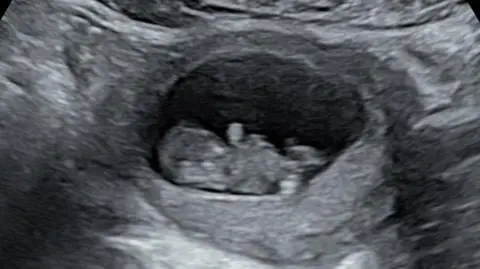

Rhiannon Lawson A scan of baby Hudson Rhiannon Lawson

Early scans of baby Hudson were initially reassuring to his mother Rhiannon

In October last year, she found out she was pregnant again and this time was reassured with some early scans.

But then came the 20-week scan, which revealed the baby boy - who the couple called Hudson - had a severe form of hypoplastic left heart syndrome.

"There was no way forward," she says, and Hudson was stillborn in March at 22 weeks.